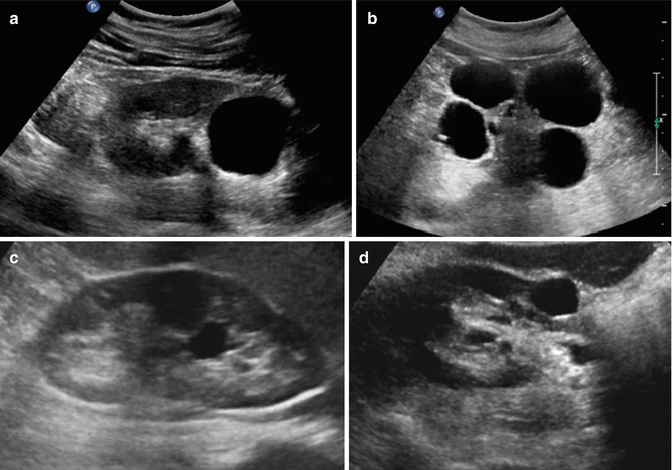

The most common cyst and other anechoic formation occur on the ovaries of young women due to fluid secretion congestion in the tissue. This paper describes a number of such lesions a Ultrasound is the method of choice in the detection and differentiation of solid or cystic masses in the abdomen. On excretory phase CT images excreted contrast material layers within the cyst.

Risk factors for having lesions that turn out to be cancerous include smoking obesity high blood pressure a family history of kidney cancer diet with fried meats or high caloric intake chronic kidney failure or dialysis. The renal cyst is of NO relevance at all. The lesion is round or oval anechoic black or without echoes has an imperceptibly thin wall and demonstrates increased sound through transmission.

Renal cell carcinoma or kidney cancer may also appear as a hypoechoic lesion and requires additional radiological testing to be properly diagnosed. If this is a simple cyst and has been seen and evaluated with an ultrasound examination the radiologist or the urologist can examine the findings and determine if it is a benign simple cyst or a more complex cyst that requires further follow up and monitoringAbout 40 of people develop simple benign kidney cysts. A renal cyst is a fluid collection in or on the kidneyThere are several types based on the Bosniak classificationThe majority are benign simple cysts that can be monitored and not intervened upon.